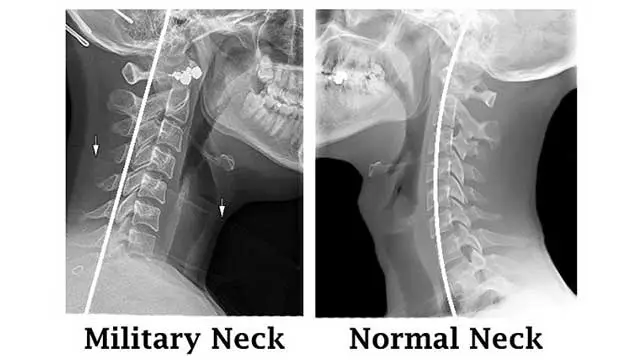

Lordoza cervikale është kurbatura natyrale e shtyllës kurrizore në nivelin e qafës, e cila shërben për të balancuar kokën, për të shpërndarë ngarkesën mekanike dhe për të mbrojtur strukturat nervore. Kur kjo kurbaturë zvogëlohet, rritet ose humbet, shfaqen probleme funksionale dhe dhimbje, duke ndikuar drejtpërdrejt në cilësinë e jetës.

• Hipo-lordoza cervikale – rrafshim i kurbës natyrale

• Humbje e lordozës (qafë e drejtë) – shpesh e lidhur me posturë të keqe dhe tension muskulor